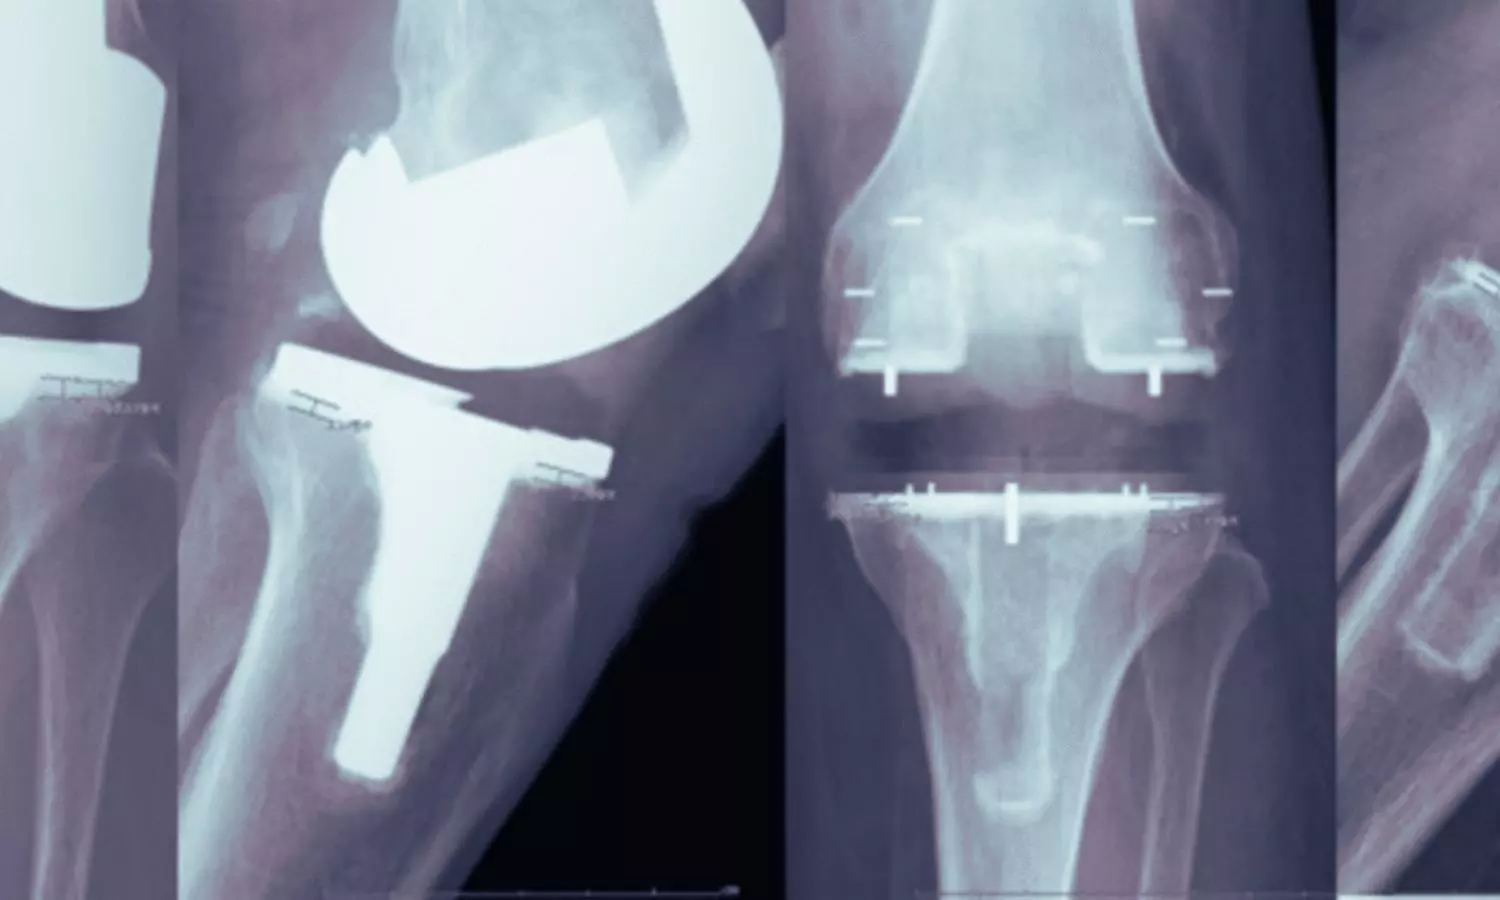

Orthopaedic implants have long depended on metals such as cobalt- chromium (Co-Cr) and titanium alloys. While mechanically strong, these materials are far stiffer than human bone, often leading to stress shielding and subsequent bone loss around implants. PEEK, by contrast, has an elastic modulus (EM) of approximately 3–4 GPa, closely resembling that of cortical bone. Emphasising this advantage, Dr (Prof) Raju Vaishya told Medical Dialogues, “PEEK is emerging as a viable, ‘bone-like’ alternative to traditional metallic implants. By closely matching the elastic modulus of human cortical bone, it significantly reduces stress shielding, which remains a major cause of implant failure.”

A key clinical advantage of PEEK highlighted in the review is its radiolucency. Unlike metal implants, PEEK does not create imaging artefacts on CT or MRI scans, allowing clearer visualisation of the bone–implant interface, and is light-weight. Coauthor Dr Abhishek Vaish explained, “The radiolucent nature of PEEK enables early detection of complications such as loosening or infection and improves postoperative monitoring.” He added that in procedures such as total knee arthroplasty, PEEK’s flexibility may promote more physiological load transfer and help preserve periprosthetic bone density.